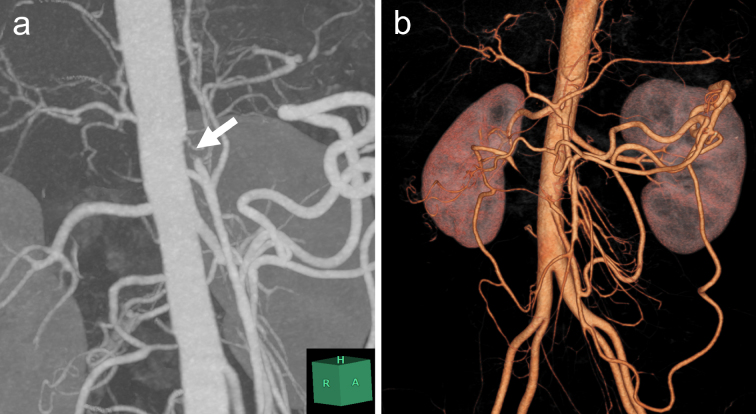

Moyamoya disease is a rare cerebrovascular occlusive disorder, and its natural course remains incompletely understood. Although rare, extracranial arterial lesions can develop in patients with moyamoya disease. We report the case of a 35-year-old Japanese woman with moyamoya disease who was referred to our department for the treatment of severe chronic mesenteric ischemia. She had a several-year history of postprandial abdominal pain and experienced two episodes of gastric ulcer perforation in the past year. Enhanced computed tomography revealed that the patient had a common trunk of the celiac and superior mesenteric arteries, which was occluded at its origin. The patient underwent an aorta to superior mesenteric artery bypass with a great saphenous vein graft. The postoperative period was uneventful, and the patient is now free of symptoms. The present case suggests that a patient with moyamoya disease can develop symptomatic mesenteric arterial lesions.